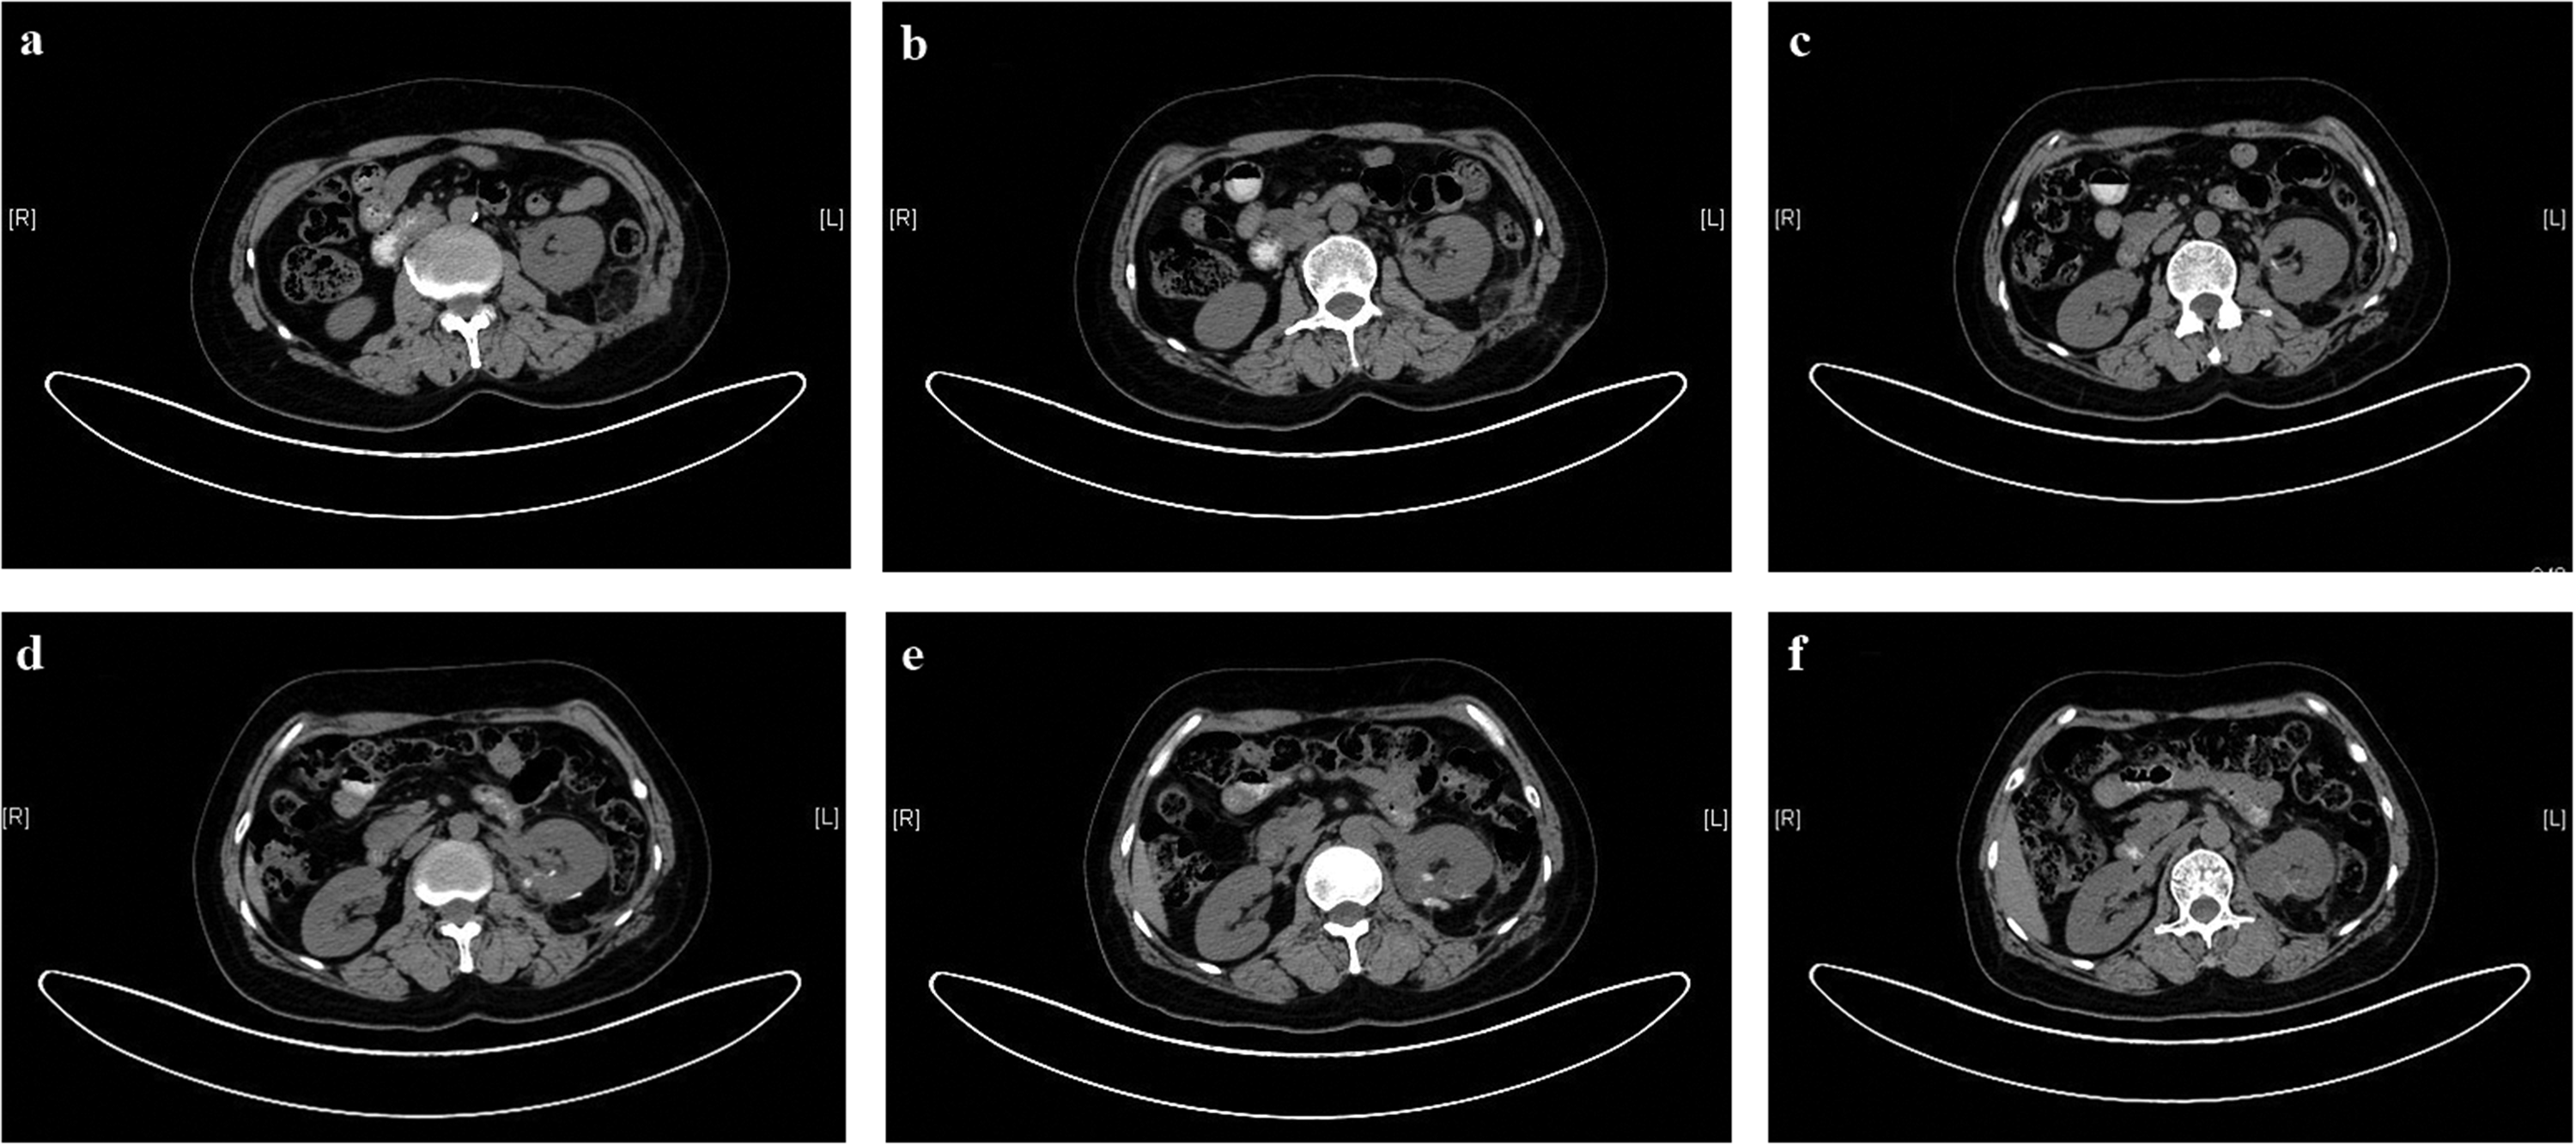

Postoperative positron emission tomography/computed tomography (PET/CT) revealed nodular lesions with tracer uptake enhancement in the left outer lobe and right anterior lobe of the liver, exhibiting a maximum standardized uptake value of approximately 13.3. However, corresponding CT imaging showed no foci with abnormal density in these areas. Because liver metastases were suspected, the patient began postoperative endocrine therapy involving intramuscular injections of octreotide acetate microspheres for injection at a dosage of 30 mg every month. At the 4-month follow-up, the patient’s condition was stable. The kidney that underwent surgical treatment showed good postoperative recovery, and there were no indications of metastatic lesions in the contralateral kidney (Figure 4).

Postoperative computed tomography images. (a)–(f) The images show good recovery of the left kidney and no metastatic lesion in the opposite kidney.